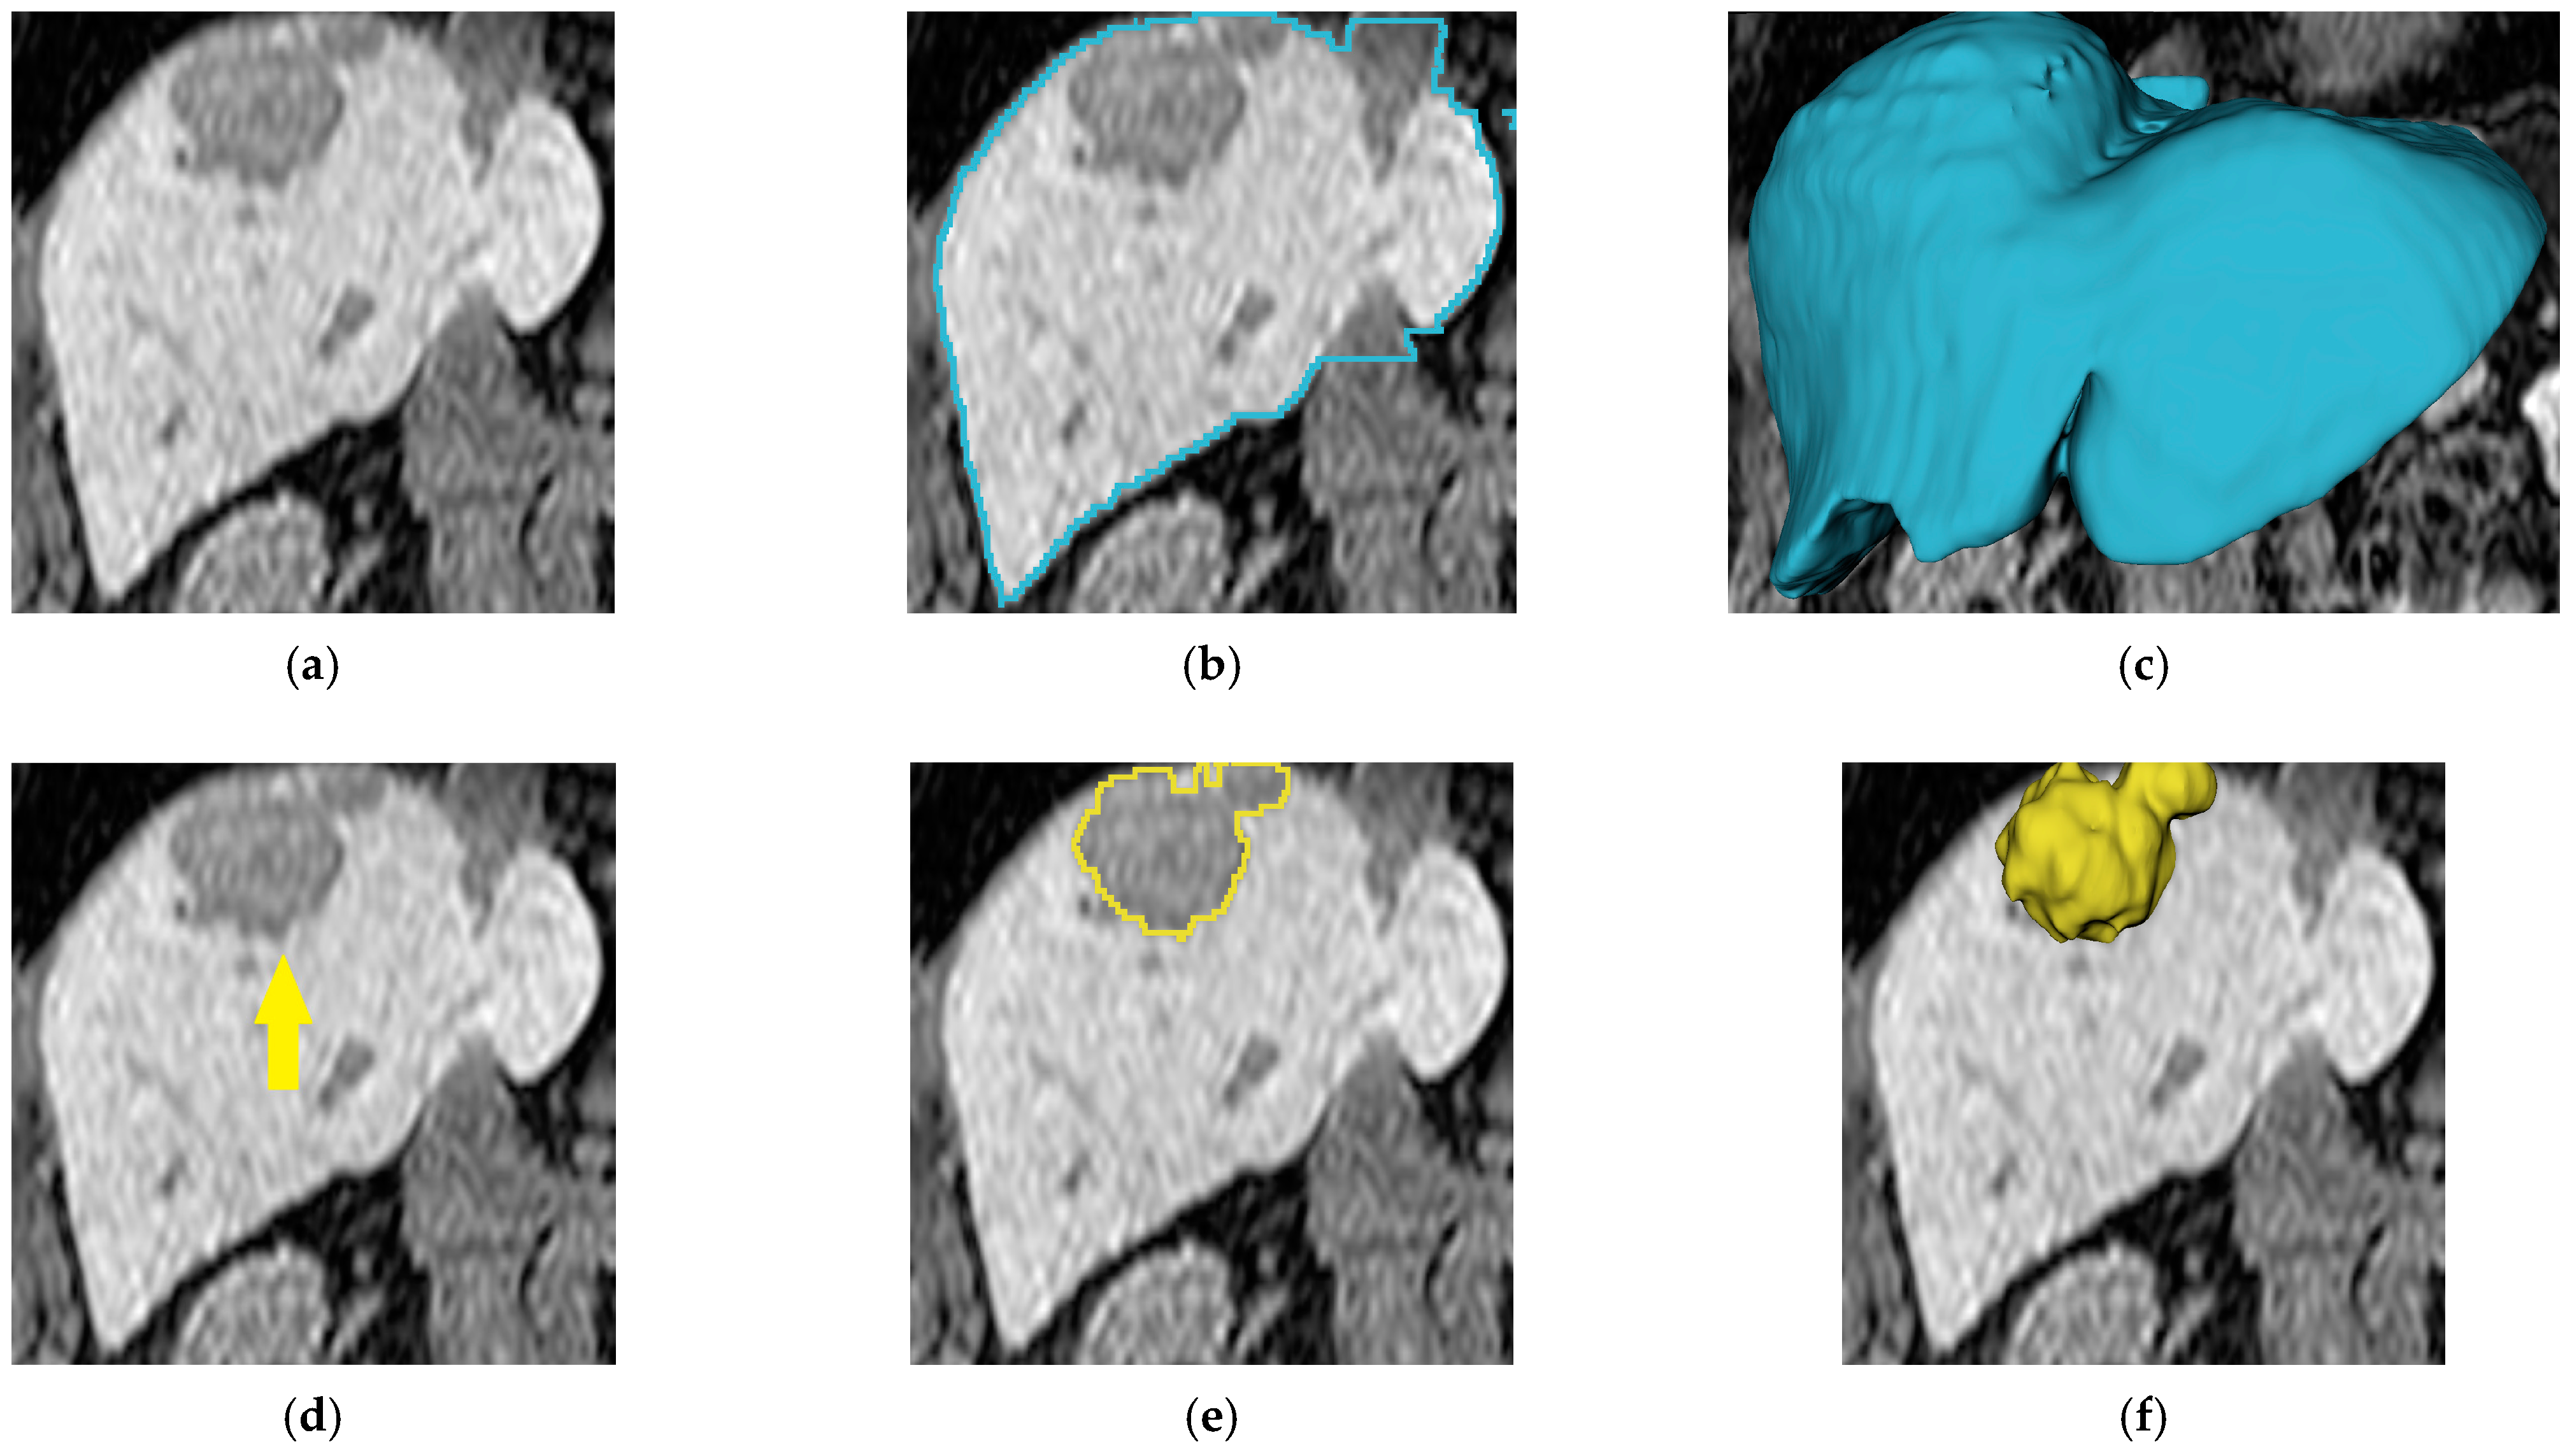

4.2.2. Qualitative Results